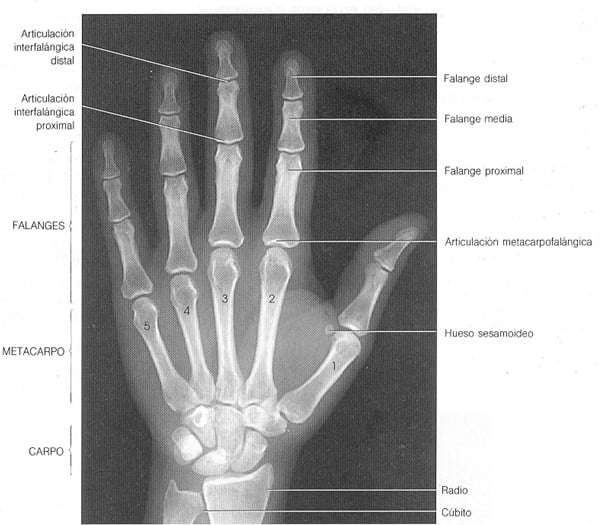

Me he medido la ratio de los dedos índice y anular para comprobar a cuanta testosterona estuve expuesto. El resultado es que tengo el anular más largo, como la mayoría de los hombres, pero es curioso, porque mi mano derecha a simple vista, el anular parece más corto que el índice pero en realidad mide más. Me lo he medido bien y de todas las formas posibles je je no hay errores. Quizás mi mano derecha hace alguna curvatura en algún sitio je je.

¿Aunque no se vea a simple vista realmente el anular es más largo no?

¿Realizo bien el experimento? Lo que te lo indica es lo que mide con centímetros no lo que se ve con el ojo humano, ¿no?